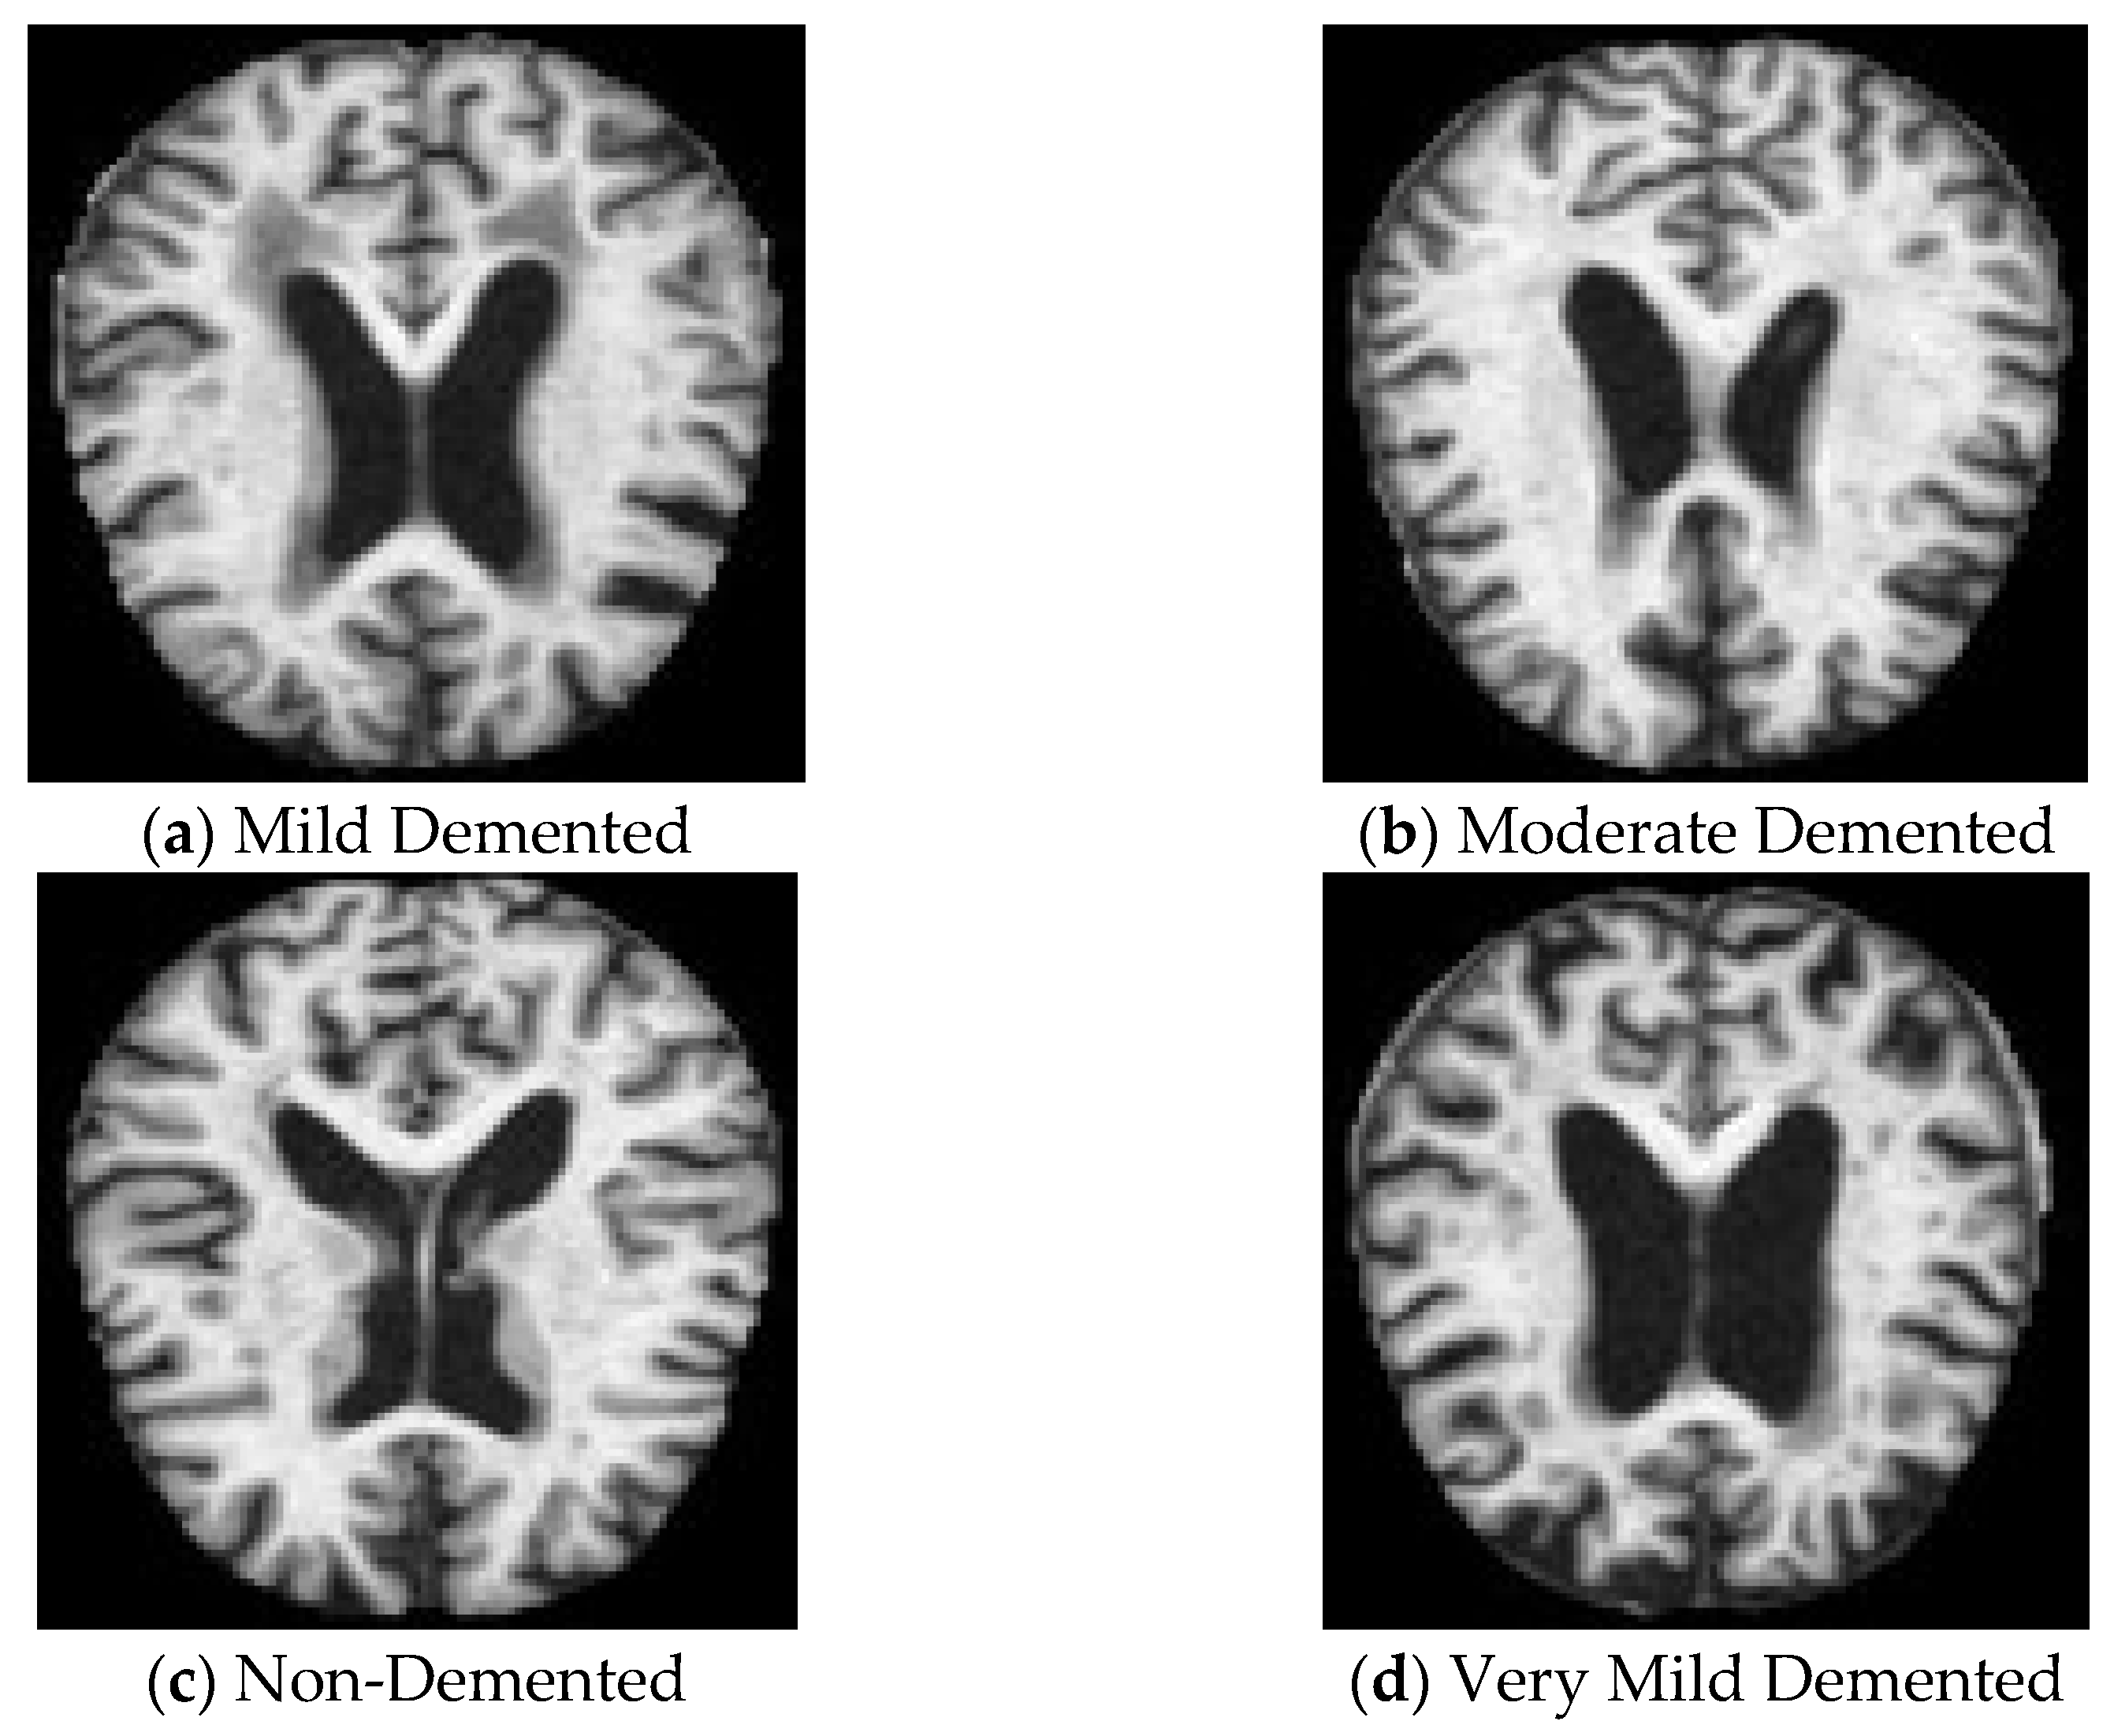

3.1. Dataset Description

| Mild Demented | 96 | 99 | 97 | 99 | 100 | 99 |

| Moderate Demented | 100 | 100 | 100 | 100 | 100 | 100 |

| Non-Demented | 99 | 98 | 98 | 100 | 99 | 100 |

| Very Mild Demented | 98 | 99 | 98 | 100 | 100 | 100 |